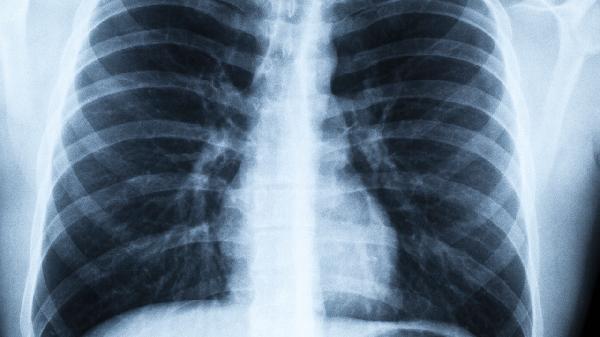

冠脈堵塞從30%到70%需要多長時間

冠脈堵塞從30%進(jìn)展到70%通常需要5-10年,具體時間與個體生活方式、基礎(chǔ)疾病控制等因素密切相關(guān)。

冠脈堵塞的進(jìn)展速度受多重因素影響。長期高脂飲食、缺乏運動、吸煙等不良習(xí)慣會加速動脈粥樣硬化進(jìn)程,可能使堵塞程度在5年內(nèi)快速惡化。高血壓、糖尿病等慢性病患者若未規(guī)范控制血糖血壓,血管內(nèi)皮持續(xù)受損,斑塊增長速度可能達(dá)到每年5%-10%。肥胖人群因代謝異常和慢性炎癥狀態(tài),冠狀動脈更容易出現(xiàn)脂質(zhì)沉積。精神壓力過大會導(dǎo)致交感神經(jīng)持續(xù)興奮,血管痙攣頻率增加,間接促進(jìn)斑塊形成。年齡增長伴隨血管彈性下降,中老年人群的冠脈狹窄進(jìn)展往往快于年輕人。

建議定期進(jìn)行冠狀動脈CT或造影檢查監(jiān)測斑塊變化,尤其存在心血管危險因素者應(yīng)每1-2年評估。日常需保持低鹽低脂飲食,每日攝入蔬菜水果不少于500克,限制紅肉和加工食品。每周進(jìn)行150分鐘以上中等強度有氧運動,如快走、游泳等。嚴(yán)格戒煙并避免二手煙暴露,控制體重使體質(zhì)指數(shù)維持在18.5-23.9之間。合并高血壓或糖尿病者需遵醫(yī)囑規(guī)律用藥,將血壓穩(wěn)定在130/80毫米汞柱以下,糖化血紅蛋白控制在7%以內(nèi)。出現(xiàn)胸悶、活動后氣促等心肌缺血癥狀時應(yīng)及時心內(nèi)科就診。